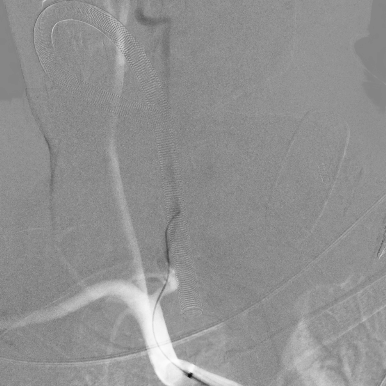

开通这么长节段的夹层所致的椎动脉,说说可以,做起来绝非易事,特别是颅内段,一旦跑到血管外出血,接近脑干,后果严重,谨慎开通的过程还算顺利,微导管带过就是磕磕绊绊不顺利,好吧,小球囊从上到下扩下来,不通,更换稍大球囊扩下来,还是不通,这夹层和狭窄不一样啊,支架导管带过仍然磕磕绊绊,不顺畅,铺开第一个支架,直接来了末端打开不良……,这么长的闭塞段,那得需要多少支架啊?万一放完了,钱花了,不通咋办?

微导管继续超过去,轻轻造影,开通的路径隐约返流闪现,立即改变策略,逆向铺路,开通成功。